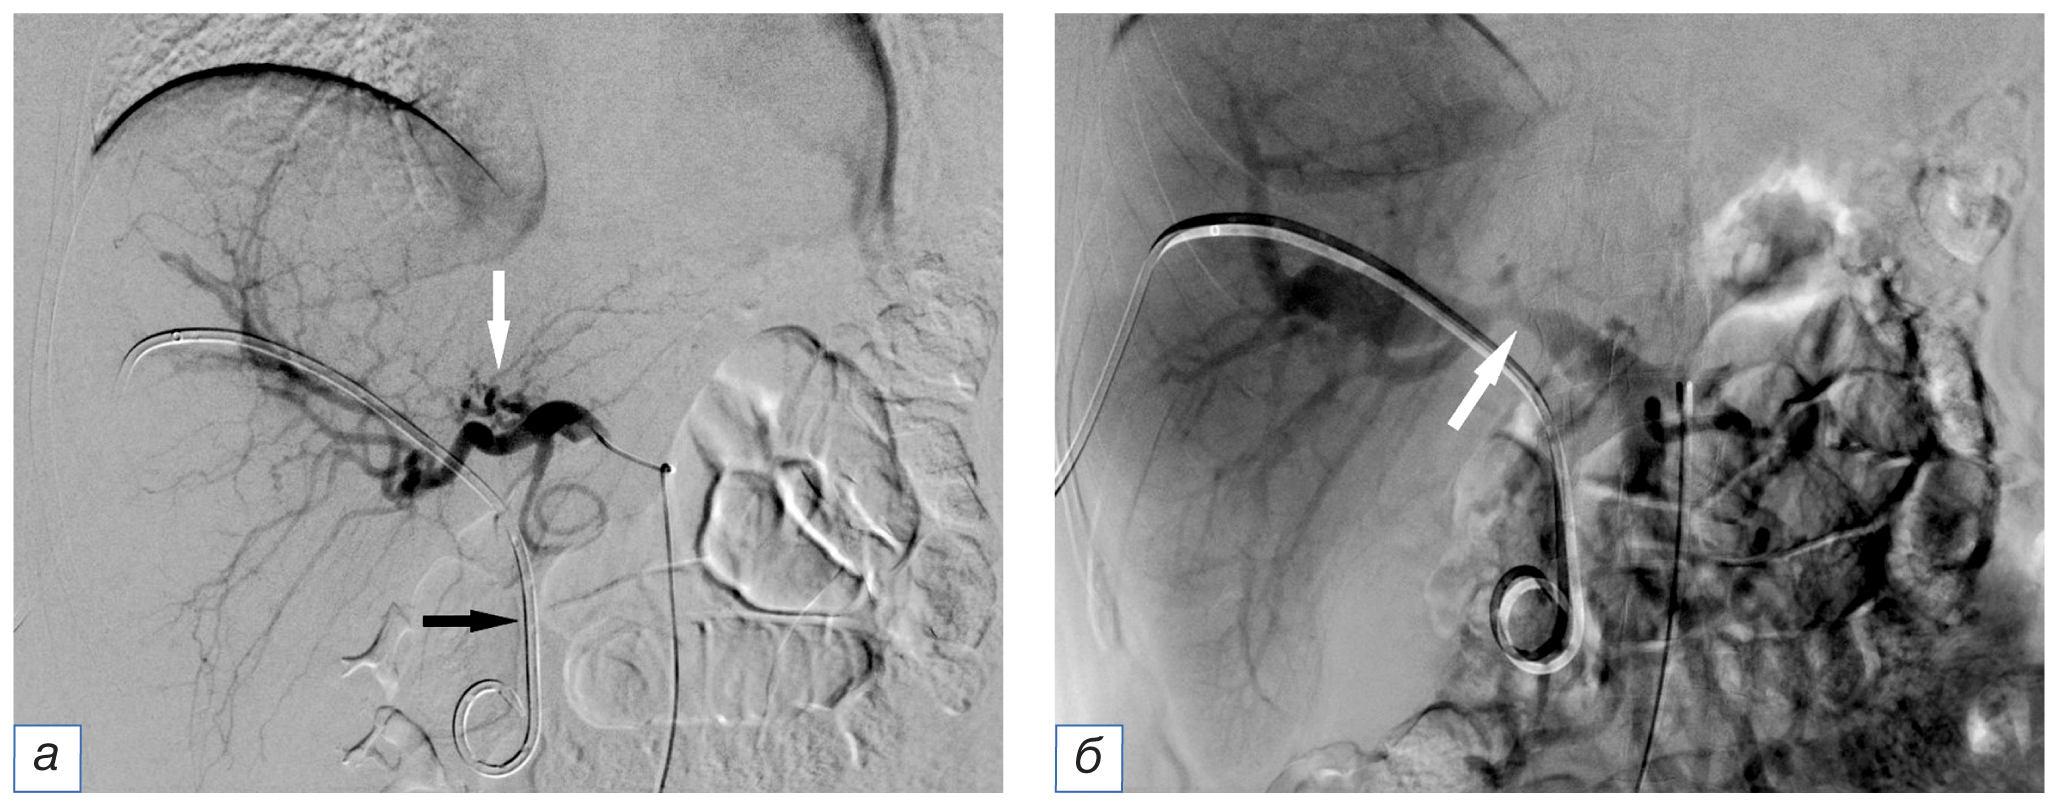

Диагностическую ангиографию выполняли по стандартной методике на столе дигитальных ангиографических комплексов Angiostar (Siemens, Германия) или Toshiba Infinix (Toshiba, Япония). Осуществляли катетеризацию бедренной артерии по Сельдингеру и ангиографию гепатопанкреатобилиарной зоны с введением контрастного вещества автоматическим шприцем (рис. 1). Использовали современные висцеральные катетеры диаметром 4–5F и проводники различной степени жесткости.

Рис. 1. Ангиограммы пациента с опухолью Клацкина, Bismuth IV: а — селективная ангиография общей печеночной артерии катетером cobra (определяется узурация ветвей левой печеночной артерии, белая стрелка); в проекции желчных протоков визуализируется наружно-внутренний холангиодренаж (черная стрелка); б — возвратная портомезентерикография (сдавление опухолью ствола воротной вены, стрелка).

Fig. 1. Patient with Klatskin tumor, Bismuth IV, angiography: а — common hepatic artery selective angiography with a cobra catheter (usuration of the branches of the left hepatic artery were determined, white arrow); in the projection of the bile ducts, external-internal cholangiodrainage is visualized (black arrow); б — recurrent portomesentericography (tumor compression of the portal vein, arrow).